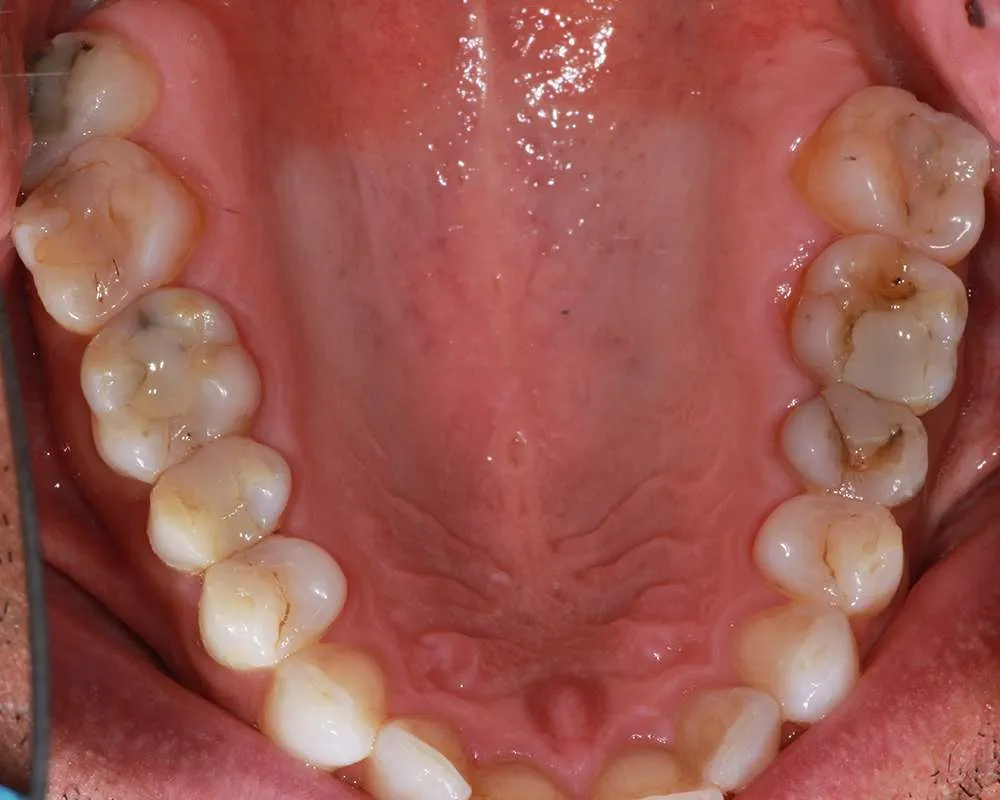

Real Stories, Real Results: Case Studies Showcasing How Our Personalized Approach Transforms Smiles and Lives

Complex Cases

Witness the Remarkable Changes We Can Achieve